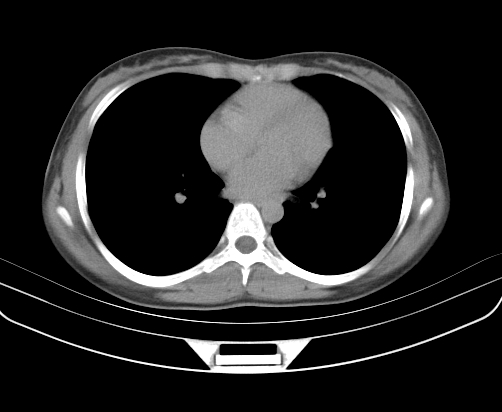

静脉期